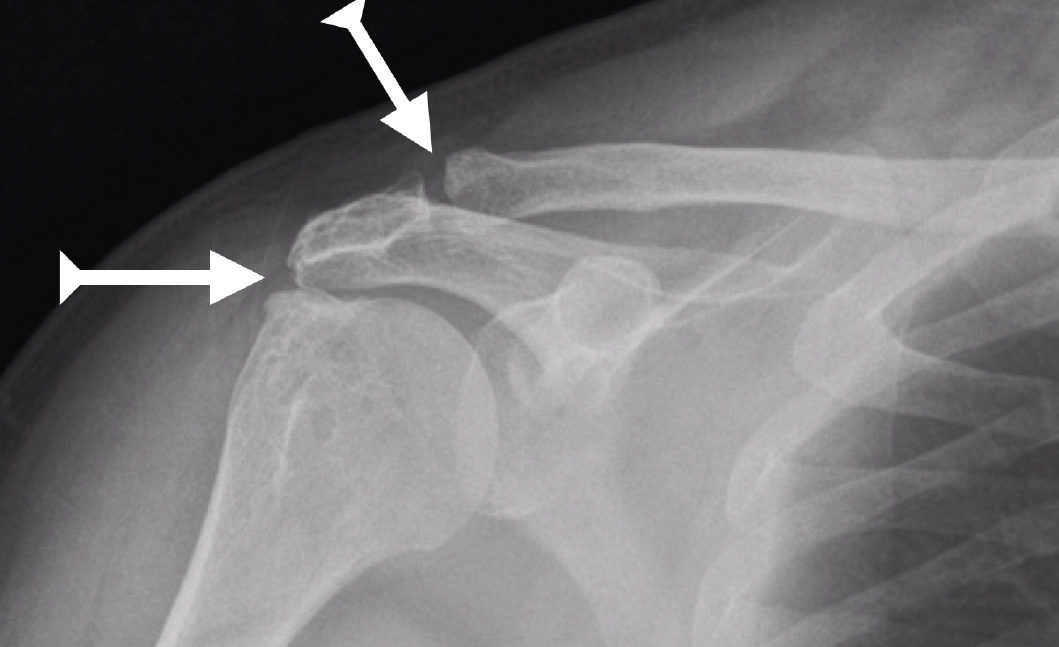

El diagnóstico clínico puede realizarse en el consultorio, sin embargo se recomienda aplicar pruebas de imagen en diferentes posiciones del hombro, como estudios de rayos X o resonancia magnética para descartar daño en los tendones del manguito rotador.

Para confirmar su diagnóstico clínico y verificar que no haya lesiones asociadas, el especialista indicará los siguientes estudios de imagen: